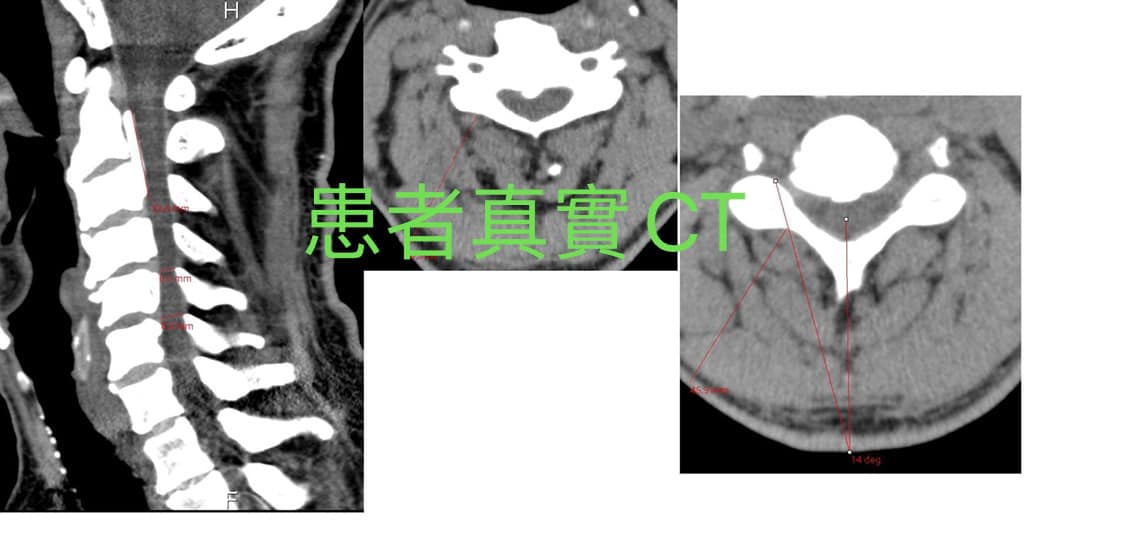

😭個案中的姜先生被此病折磨到半年以上都無法入睡,睡覺跟開車與工作整個右手跟右肩膀都麻到不行,右側肩膀肌肉還有一點小萎縮,從小診所看到醫學中心,原本預定今年五月十二號在台北某醫學中心動刀,最後一刻還是暫時延後手術,來門診諮詢跟嘗試治療,他說看過三個神外醫師其中兩個都是教授等級,都建議開刀,自己內心也會害怕開刀,其實徐醫師看過姜先生的CT之後,也做過評估,治療三周如果症狀減輕就繼續,如果沒改善就在月底維持動刀(椎板切除與椎板成形術)

👌評估:後縱韌帶鈣化引起椎管狹窄